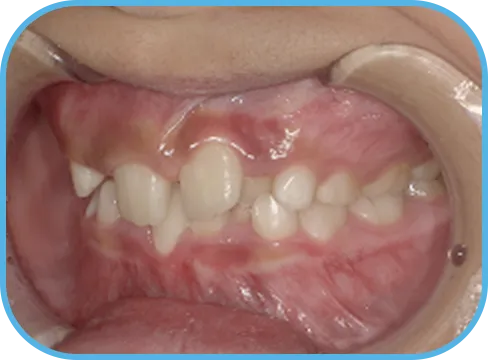

• Before

• 正 面

治療前正面からの歯の様子

• 上 顎

治療前上顎からの歯の様子

• 下 顎

治療前下顎からの歯の様子

• 右 側

治療前右側からの歯の様子

• 左 側

治療前左側からの歯の様子

主 訴

前歯ガタガタ、前歯が大きい

治療内容

インビザライン・ファースト

治療期間

7か月

治療費(税別)

450,000円+診断料5,000円

リスク・副作用

• 親知らずの影響や加齢などによって、凸凹が生じる可能性があります。

• 治療の初期段階では痛みや不快感が生じやすくなりますが、1週間前後で慣れます。

• 顎の成長発育によって、噛み合わせや歯並びが変化する可能性があります。

• 状況により当初予定した治療計画を変更する可能性があります。